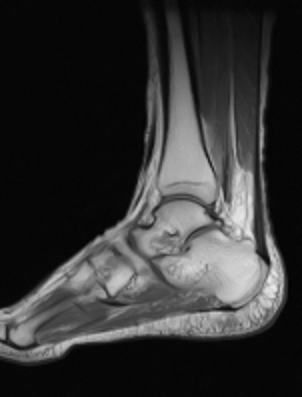

整形外科時代の先輩にその話をすると「そら完全に半月板切れてるな! 手術しかないで!」と言われてしまいましたが、いざ自分がされる側になるとやっぱり手術はいやなので様子を見ていると、徐々にましになってきてほっとしたのも束の間…その次は左の足の裏が痛くなり、朝起きると30分ほど痛くて歩きづらい事が2回ほどあっておかしいなと思っていると、今度は足首の内側が腫れてきました。少し赤くて押さえるとちょっと痛かったので、最初は何か炎症かな?と思って湿布したりしてたんですが、治まるどころか膨らんできたので、心配になってきました。腫瘍でしかも悪性やったらやばいやん! 下腿切断の危機か?? さすがに悪性腫瘍だとまずいので、整形外科時代の5年後輩で腫瘍を専門にしているM君に久しぶりに連絡してみると、5日後にMRIの予約を取ってくれました。M君は知らないうちに大阪の結構大きなM病院の副院長になっててびっくり。普通はその規模の病院だとMRIの予約なんて1か月は先になってしまうので、やっぱり持つべきものは後輩ですね。その後思いついて検査の日までプラセンタ点滴を続けてみると、膨らみが少し小さくなってきたので腫瘍ではないのかなとは思ったんですが、念のために検査は受ける事にしました。悪友Mなんかには「足切断したら最新技術駆使してスケートボード付き義足でも付けたら? 歩くのが早くなって返って便利かもよ」なんて笑い飛ばされたけど。

しばらくして「ご無沙汰してます!」とM君が。私が開業してから会ってなかったので、なんと16年ぶりの再会です。診察してもらってMRIも診てもらったところ、「MRIは足関節内果から足底にかけて白っぽく炎症のような所見はありますけど、腫瘍はありませんね」良かった~!! 「まぁ悪性やったらそこまで急激な増大は少ないんで、炎症やと思いますけど…。何か動き過ぎました?」う~ん、心当たりと言えばクリニックに溜まった書類を片付けたくらいなんだけど…。それくらいでこんな炎症を起こすなんて、やっぱり年かなぁ。まぁ腫瘍はないという事でほっとして、M君とひとしきり懐かしい整形外科話。私が開業した時に教授になったK先生がついに退官し、またもや白い巨塔のような教授選が近々繰り広げられるらしい。M君は16年前よりちょっぴり老けてたけど、それほどではなかったので「M君も変わらんね」と言うと、「先生こそ全然変わりませんやん。美容に転向して正解やったんちゃいます?」そう言われたのは嬉しかったな…(^_^)。 そんなこんなで色々あって、自分自身の人生を真剣に振り返るきっかけとなりました。そしてこれは3度目の人生の転機だと確信するに至ります。(突然思ったのではなく、ずっと考えていて決断の時だと確信した…という事なんですけど。)